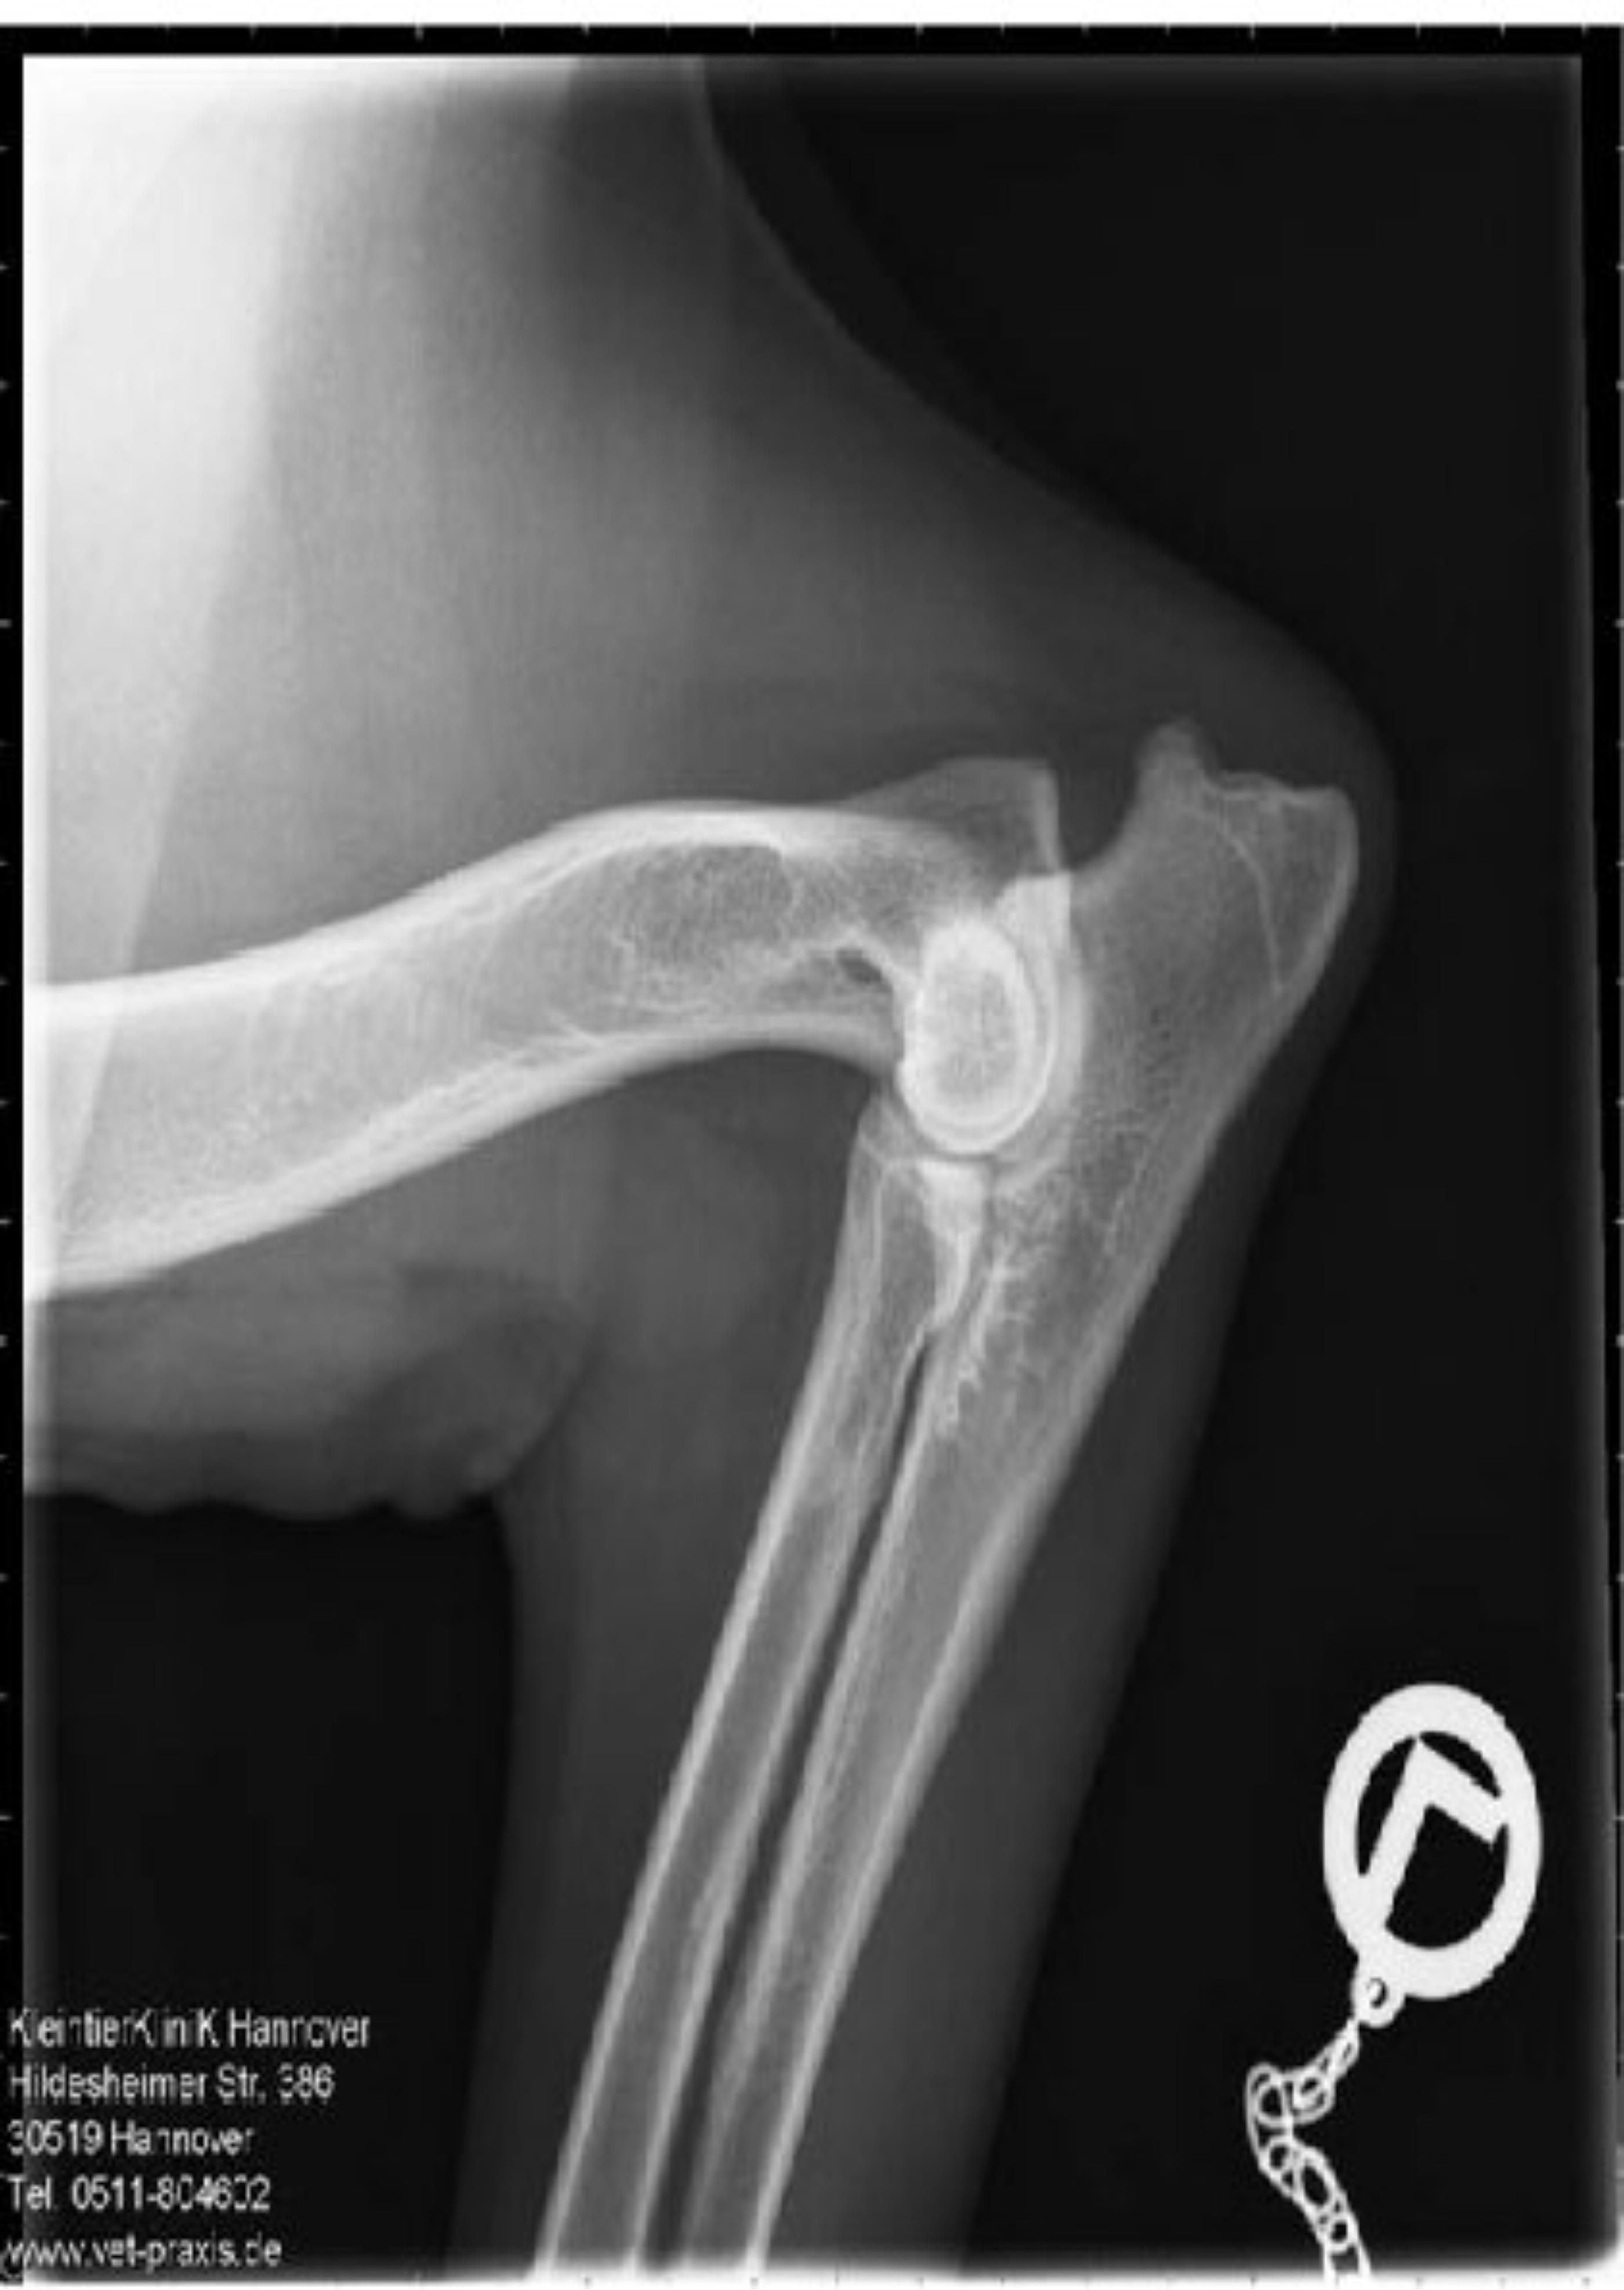

ED - OCD - Röntgenaufnahme